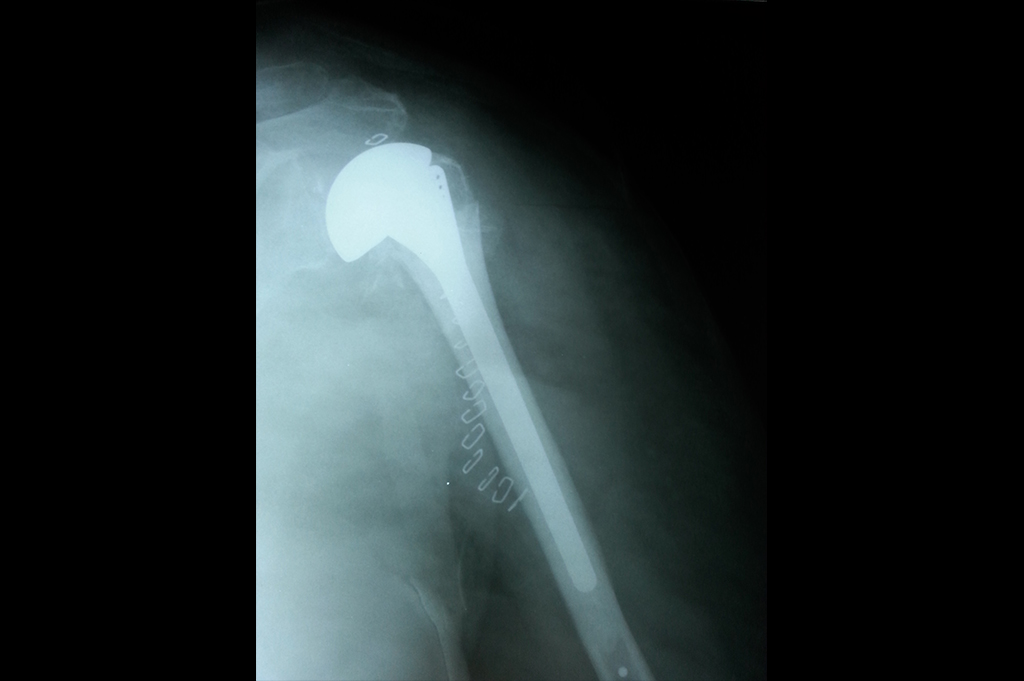

Shoulder Replacement